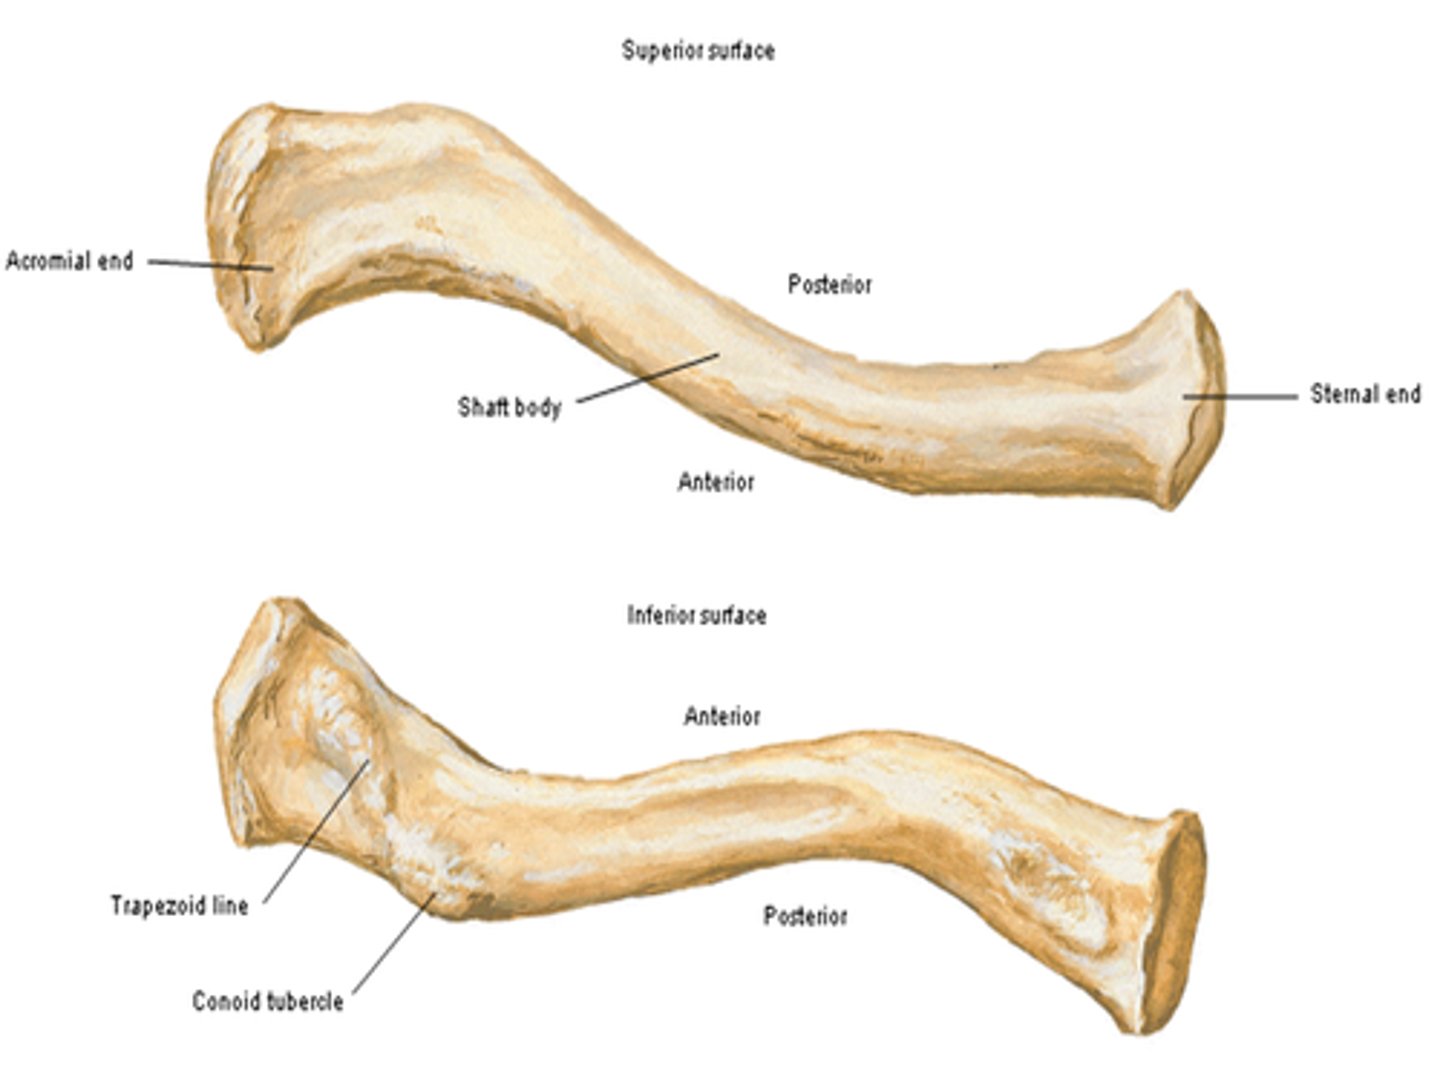

Parts of the clavicle:

- shaft

- superior surface

- inferior surface

Shaft of the clavicle:

double curved in the horizontal plane, which increases resilience

Middle half of the shaft of the clavicle:

convex anteriorly, and lateral half concave anteriorly

Sternal end of the shaft of the clavicle articulates:

articulates with manubrium via the sternoclavicular joint

Acromial end of the shaft of the clavicle articulates:

articulates with acromion via acromioclavicular joint

Location of superior surface of the clavicle:

lies deep to the platysma muscle and skin and it is smooth

Inferior surface of the clavicle:

rough surface with ligaments binding to it

Location of conoid tubercle of the inferior surface of the clavicle:

near acromial end of clavicle

Function of conoid tubercle on the inferior surface of the clavicle:

support for the medial part of the coracoclavicular ligament

Location of the trapezoid line of the inferior surface of the clavicle:

nearer to the acromial end than the conoid tubercle

Function of the trapezoid line of the inferior surface of the clavicle:

support for the lateral part of the coracoclavicular joint